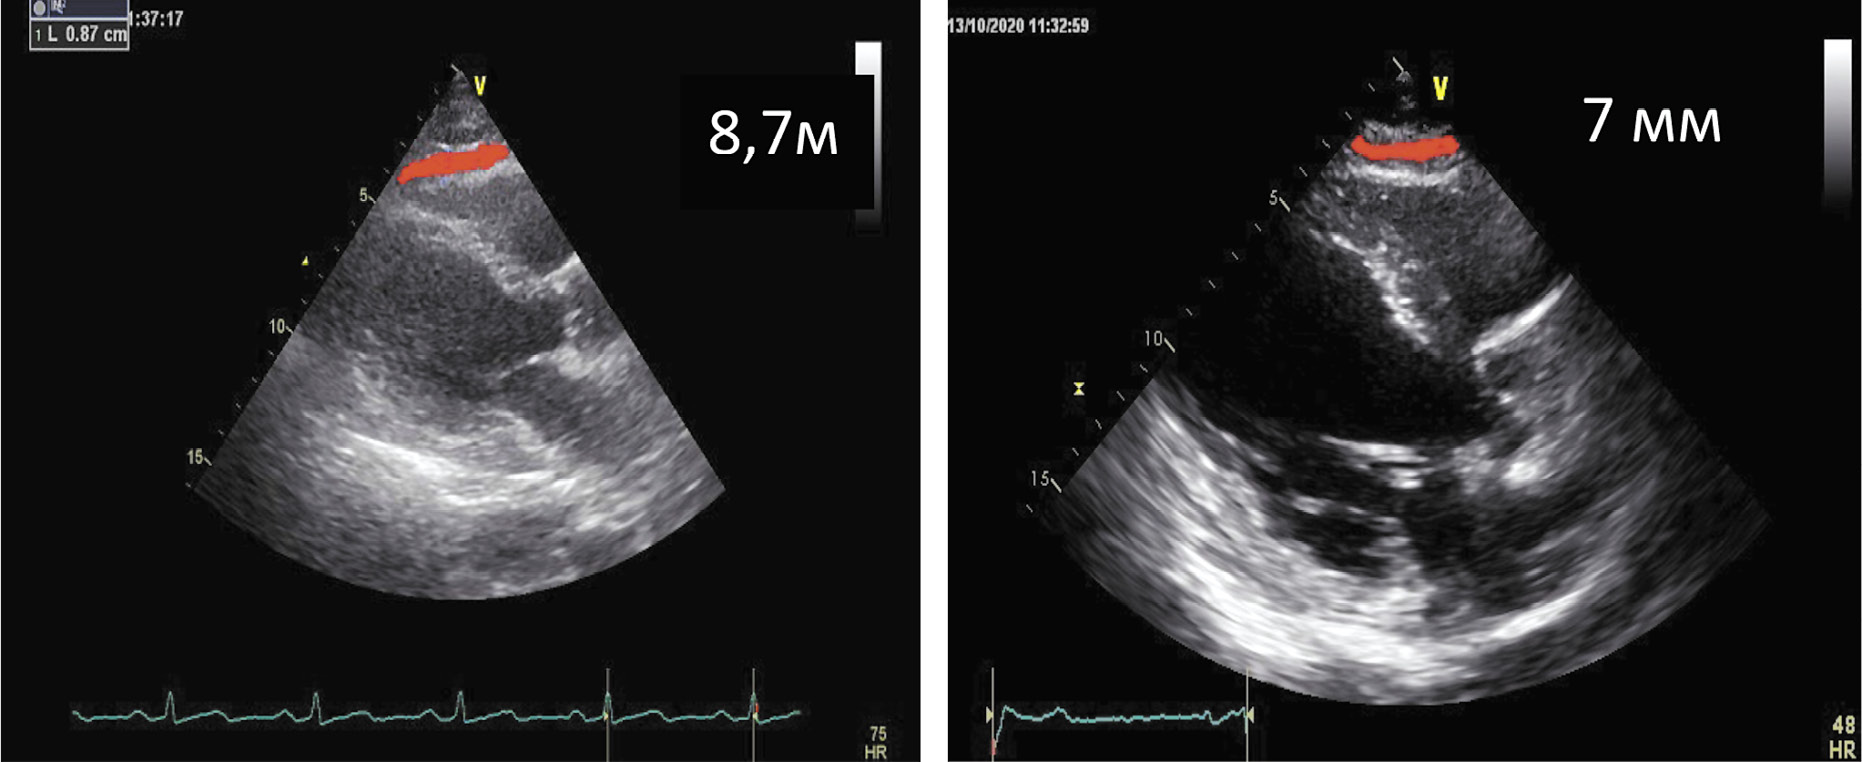

Толщина эпикардиального жира в систолу, мм | 8,7 | 7 |

Толщина эпикардиального жира в диастолу, мм | 4 | 3 |

Также важно отметить уменьшение толщины ЭЖТ как в систолу (до 7 мм), так и в диастолу (до 3 мм); рис. 2.

Рис. 2. Толщина ЭЖТ в систолу ЛЖ до и после лечения семаглутидом.